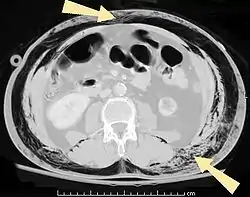

![]() مقطع عرضي للبطن بالأشعة المقطعية لمريض مُصاب بنفاخ تحت الجلد (مشارًا إليها بالأسهم) مقطع عرضي للبطن بالأشعة المقطعية لمريض مُصاب بنفاخ تحت الجلد (مشارًا إليها بالأسهم) | |

من السهل تشخيص الحالات الكبيرة من نفاخ تحت الجلد بسبب العلامات المميزة لهذه الحالة.[1] في بعض الحالات، تكون العلامات خفية مما يجعل التشخيص أكثر صعوبة.[11] يُستَخدم التصوير الطبي لتشخيص الحالة أو لتأكيد التشخيص السريري. في الصورة الإشعاعية الصدرية، قد يظهر نفاخ تحت الجلد كحزوزٍ إشعاعيةٍ شفافة في النمط المتوقع لمجموعة العضلات الصدرية الكبرى. قد يتداخل الهواء في الأنسجة تحت الجلدية مع التصوير الإشعاعي للصدر، مما يُخفي حالاتٍ خطيرة مثل استرواح الصدر.[26] قد يقلل أيضًا من فعالية الموجات فوق الصوتية في الصدر.[27] من ناحية أخرى، بما أن نفاخ تحت الجلد قد يظهر بوضوح في الأشعة السينية للصدر قبل أن يحدث استرواح الصدر، يمكن استخدام وجوده للدلالة على حدوث الإصابة الأخيرة.[11] يمكن رؤية النفاخ تحت الجلد أيضًا في الأشعة المقطعية، حيث تظهر تجمعات الهواء تحت الجلد كمساحاتٍ مظلمة. يُعتبر التصوير المقطعي دقيق جدًا، حيث يجعل من السهل العثور على البقعة الدقيقة التي يدخل منها الهواء إلى الأنسجة الرخوة.[11] في عام 1994، نشر ماكلين مزيدًا من الأفكار حول الفيزيولوجيا المرضية لمتلازمة ماكلين التلقائية، والتي تحدث نتيجة لنوبةٍ حادةٍ من الربو.